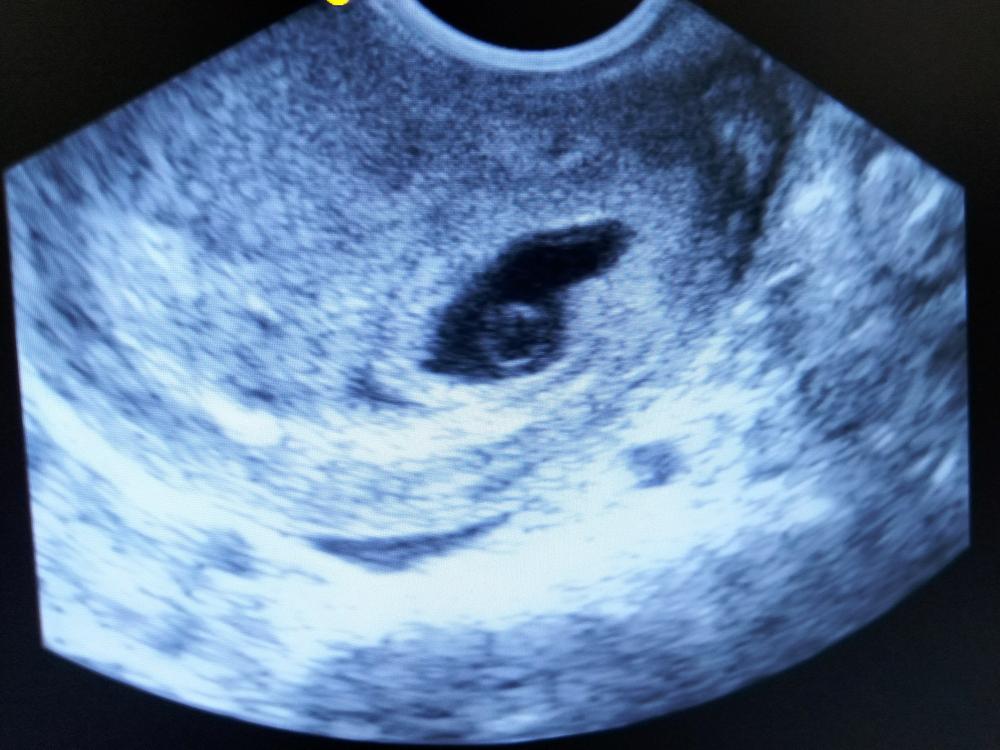

Trên hình ảnh siêu âm thai, hình ảnh yolksac sẽ có hình dạng một túi nhỏ, có thể có bờ rõ nét. Lúc này phôi thai có thể đang chuẩn bị hình thành hoặc mới hình thành nhưng chưa nhìn thấy được.